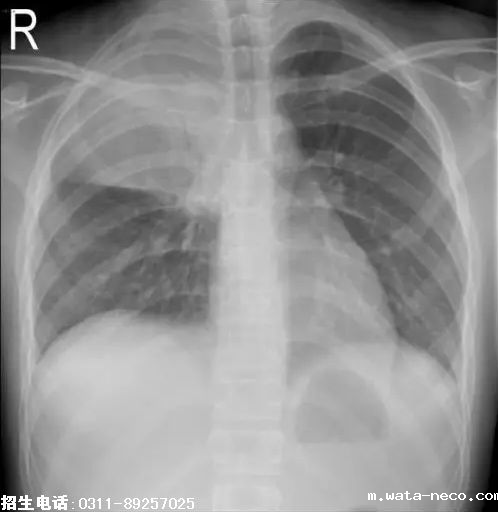

4、题干:男,10岁。发热、咳嗽6天。结合X线片,此诊断为

A、气胸

B、正常胸片

C、大叶性肺炎

D、肺结核

E、肺癌

答案:C

解析:大叶性肺炎表现为肺透亮度轻度下降或密度稍高的模糊影,均匀的致密影。肺炎累及整个肺叶时,以叶间裂为界,边缘清楚,形态与肺叶一致。(C对)